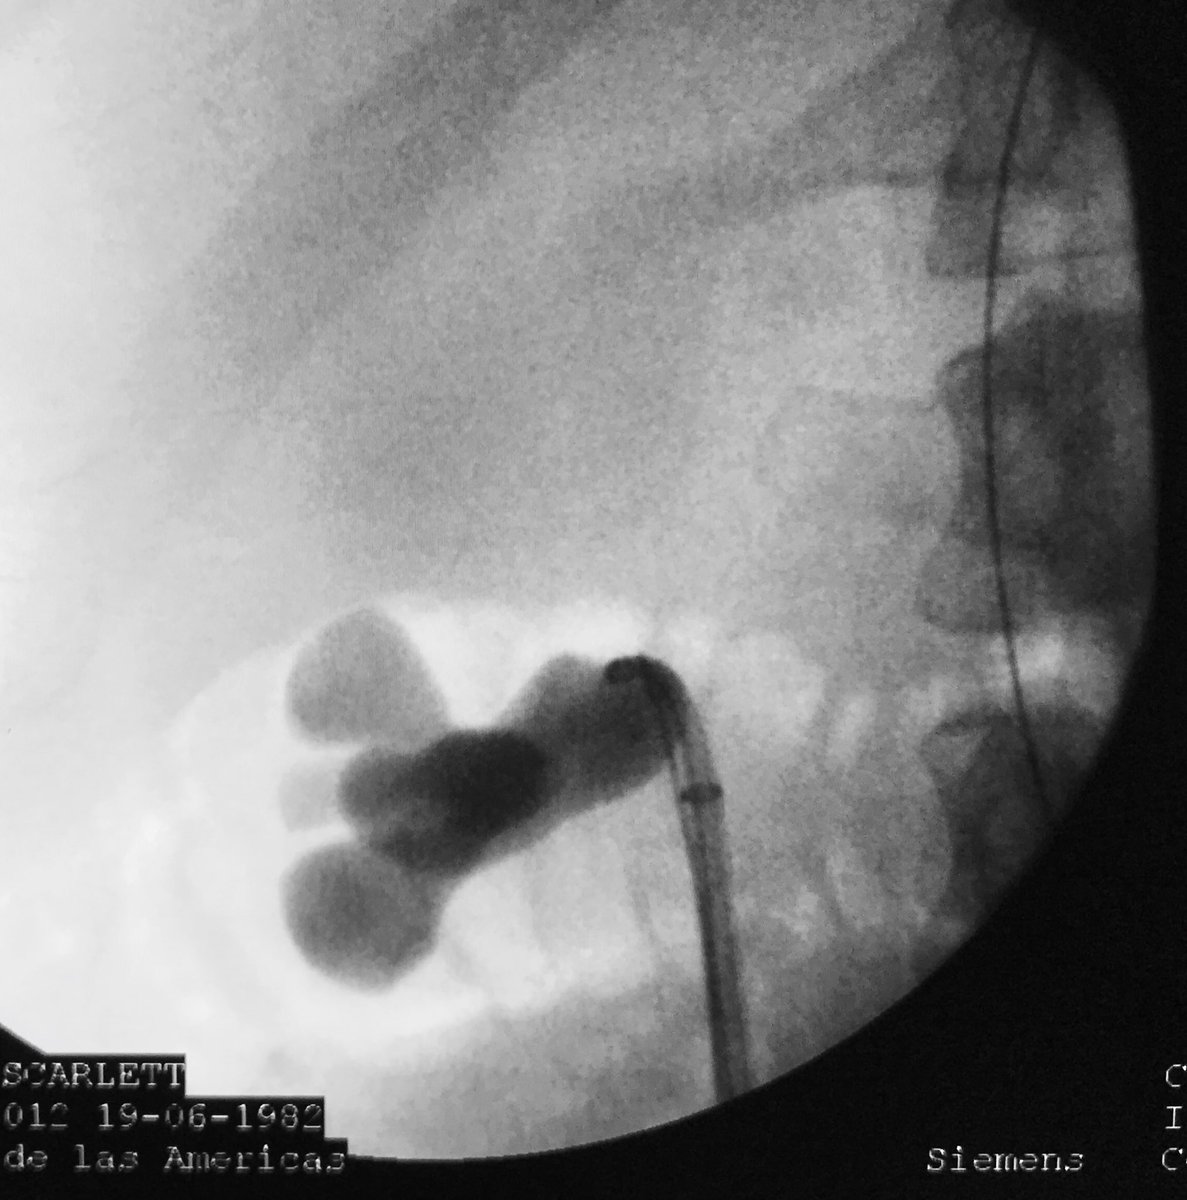

PCNL challenges

Eduardo Cruz-Nuricumbo MD Professor endourology